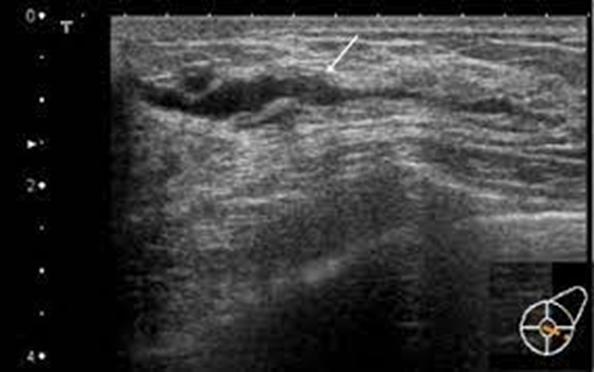

What is this image showing?

ductal carcinoma in situ